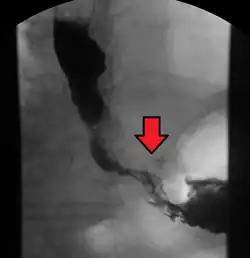

Although an occlusive tumor may be suspected on a barium swallow or barium meal, the diagnosis is best made with an examination using an endoscope. This involves the passing of a flexible tube with a light and camera down the esophagus and examining the wall, and is called an esophagogastroduodenoscopy. Biopsies taken of suspicious lesions are then examined histologically for signs of malignancy.

Additional testing is needed to assess how much the cancer has spread (see § Staging, below). Computed tomography (CT) of the chest, abdomen and pelvis can evaluate whether the cancer has spread to adjacent tissues or distant organs (especially liver and lymph nodes). The sensitivity of a CT scan is limited by its ability to detect masses (e.g. enlarged lymph nodes or involved organs) generally larger than 1 cm.[44][45] Positron emission tomography is also used to estimate the extent of the disease and is regarded as more precise than CT alone.[46] PET/MR as a novel modality has shown promising results in preoperative staging with fair feasibility and good correlation in comparison to PET/CT. It can enhance tissue differentiation with lowering the radiation dose to the patient.[47] Esophageal endoscopic ultrasound can provide staging information regarding the level of tumor invasion, and possible spread to regional lymph nodes.

Contrast CT scan showing an esophageal tumor (axial view)

Contrast CT scan showing an esophageal tumor (coronal view)